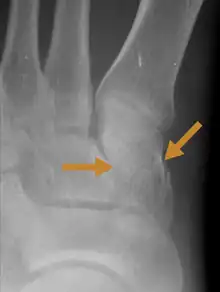

An X-ray of a Medial cuneiform fracture

A Cuneiform fracture is an injury of the foot in which one or more of the Cuneiform bones are fractured.[2] The annual incidence of cuboid fracture is 1.8 injuries per 100,000 population.[3]